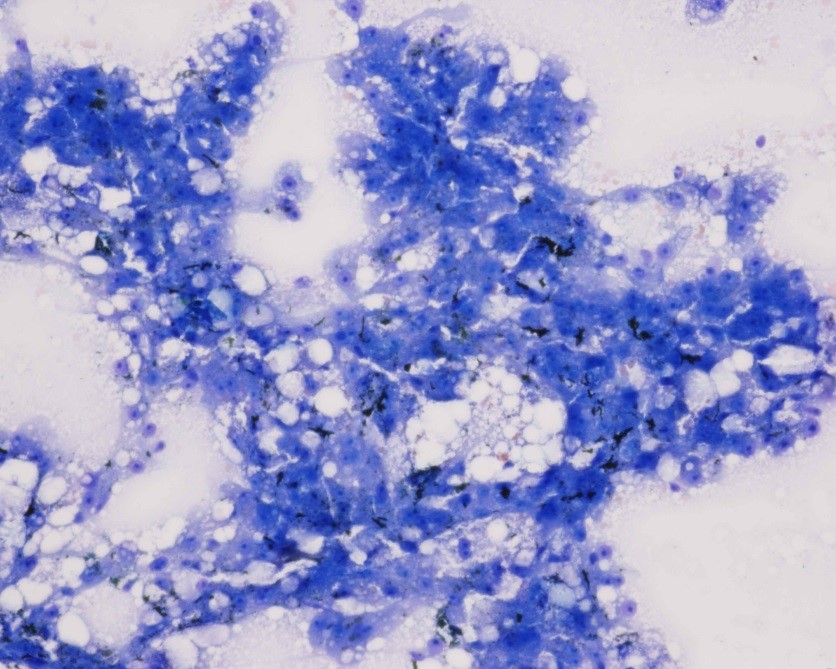

Cytology of fine-needle liver biopsy: Highly cellular sample contains hepatocytes with marked vacuolation and extracellular bile casts.

Low Power view